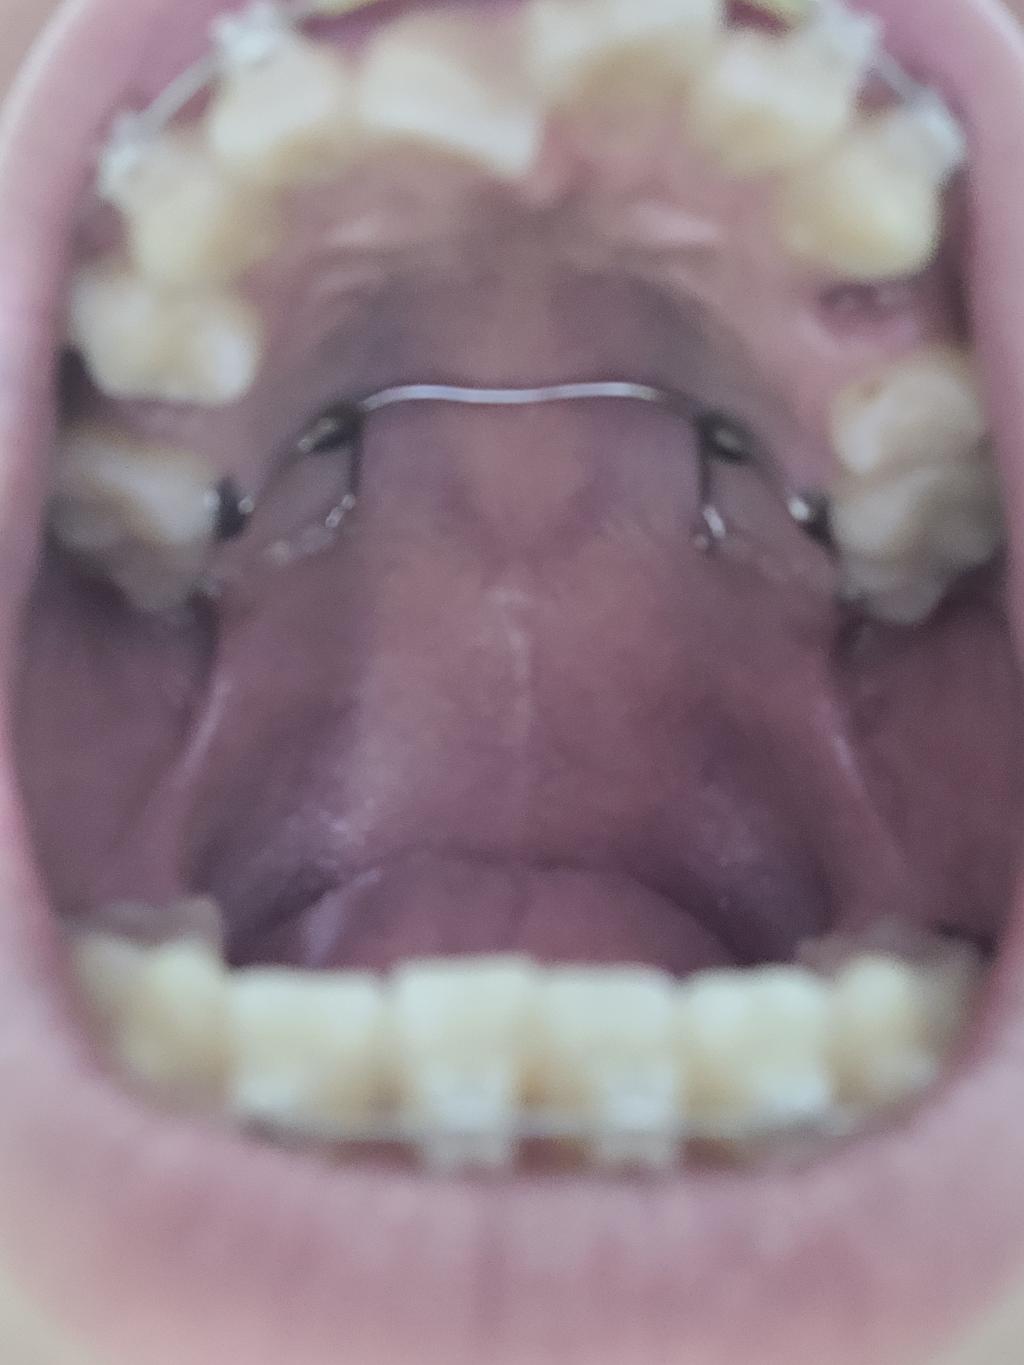

녜, 이런 디자인을 TPA(TransPalatal Archwire)라고 하는데요, 굳이 번역한다면 "입천장 가로지르는 철사"라고 할 수 있겠네요.

아마도 교정선생님께서 교정치료 중에 큰 어금니가 앞으로 쏠려 나가지 않게 하려고 만드신거 같네요. 즉 이를 뺀자리로 앞니들을 이동시키려고 하는데 큰 어금니가 앞으로 끌려가서 앞니들이 뒤로 이동할 공간을 잡아먹어 앞니들이 충분히 뒤로 이동하지 못할까봐 만들어 주신 것이라 생각합니다.

대부분의 경우는 한 3개월 정도 지나시면 적응을 하시고 말을 할때나 식사 할때도 그리 힘들어하지 않으시는데 아마도 좀 힘들어 하시는 분 중에 한 분이신거 같네요. 좋은 치료 결과를 위해서 하는 것이니 좀 힘드시지만 참아보시는 것이 좋을것 같은데 너무 힘드시면 치료해주시는 선생님한테 말씀 드리고 다른 방법을 찾아보셔야 겠네요.